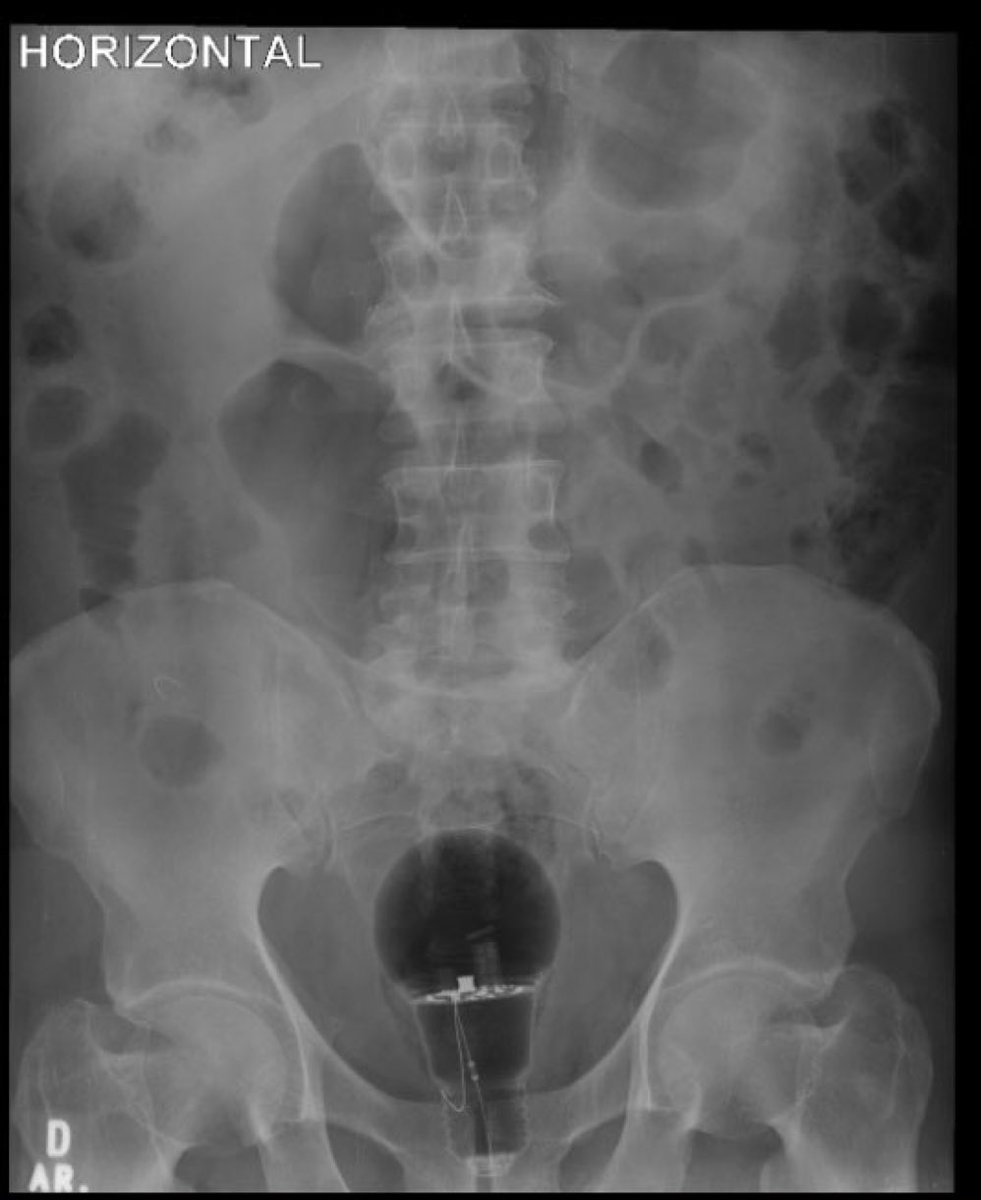

Does anybody have any bright ideas for removing this? (Via @eljulii37)

@drkeithsiau @eljulii37 Never mind getting it out….my ten year old daughter just saw me look at this and asked how the individual swallowed it?